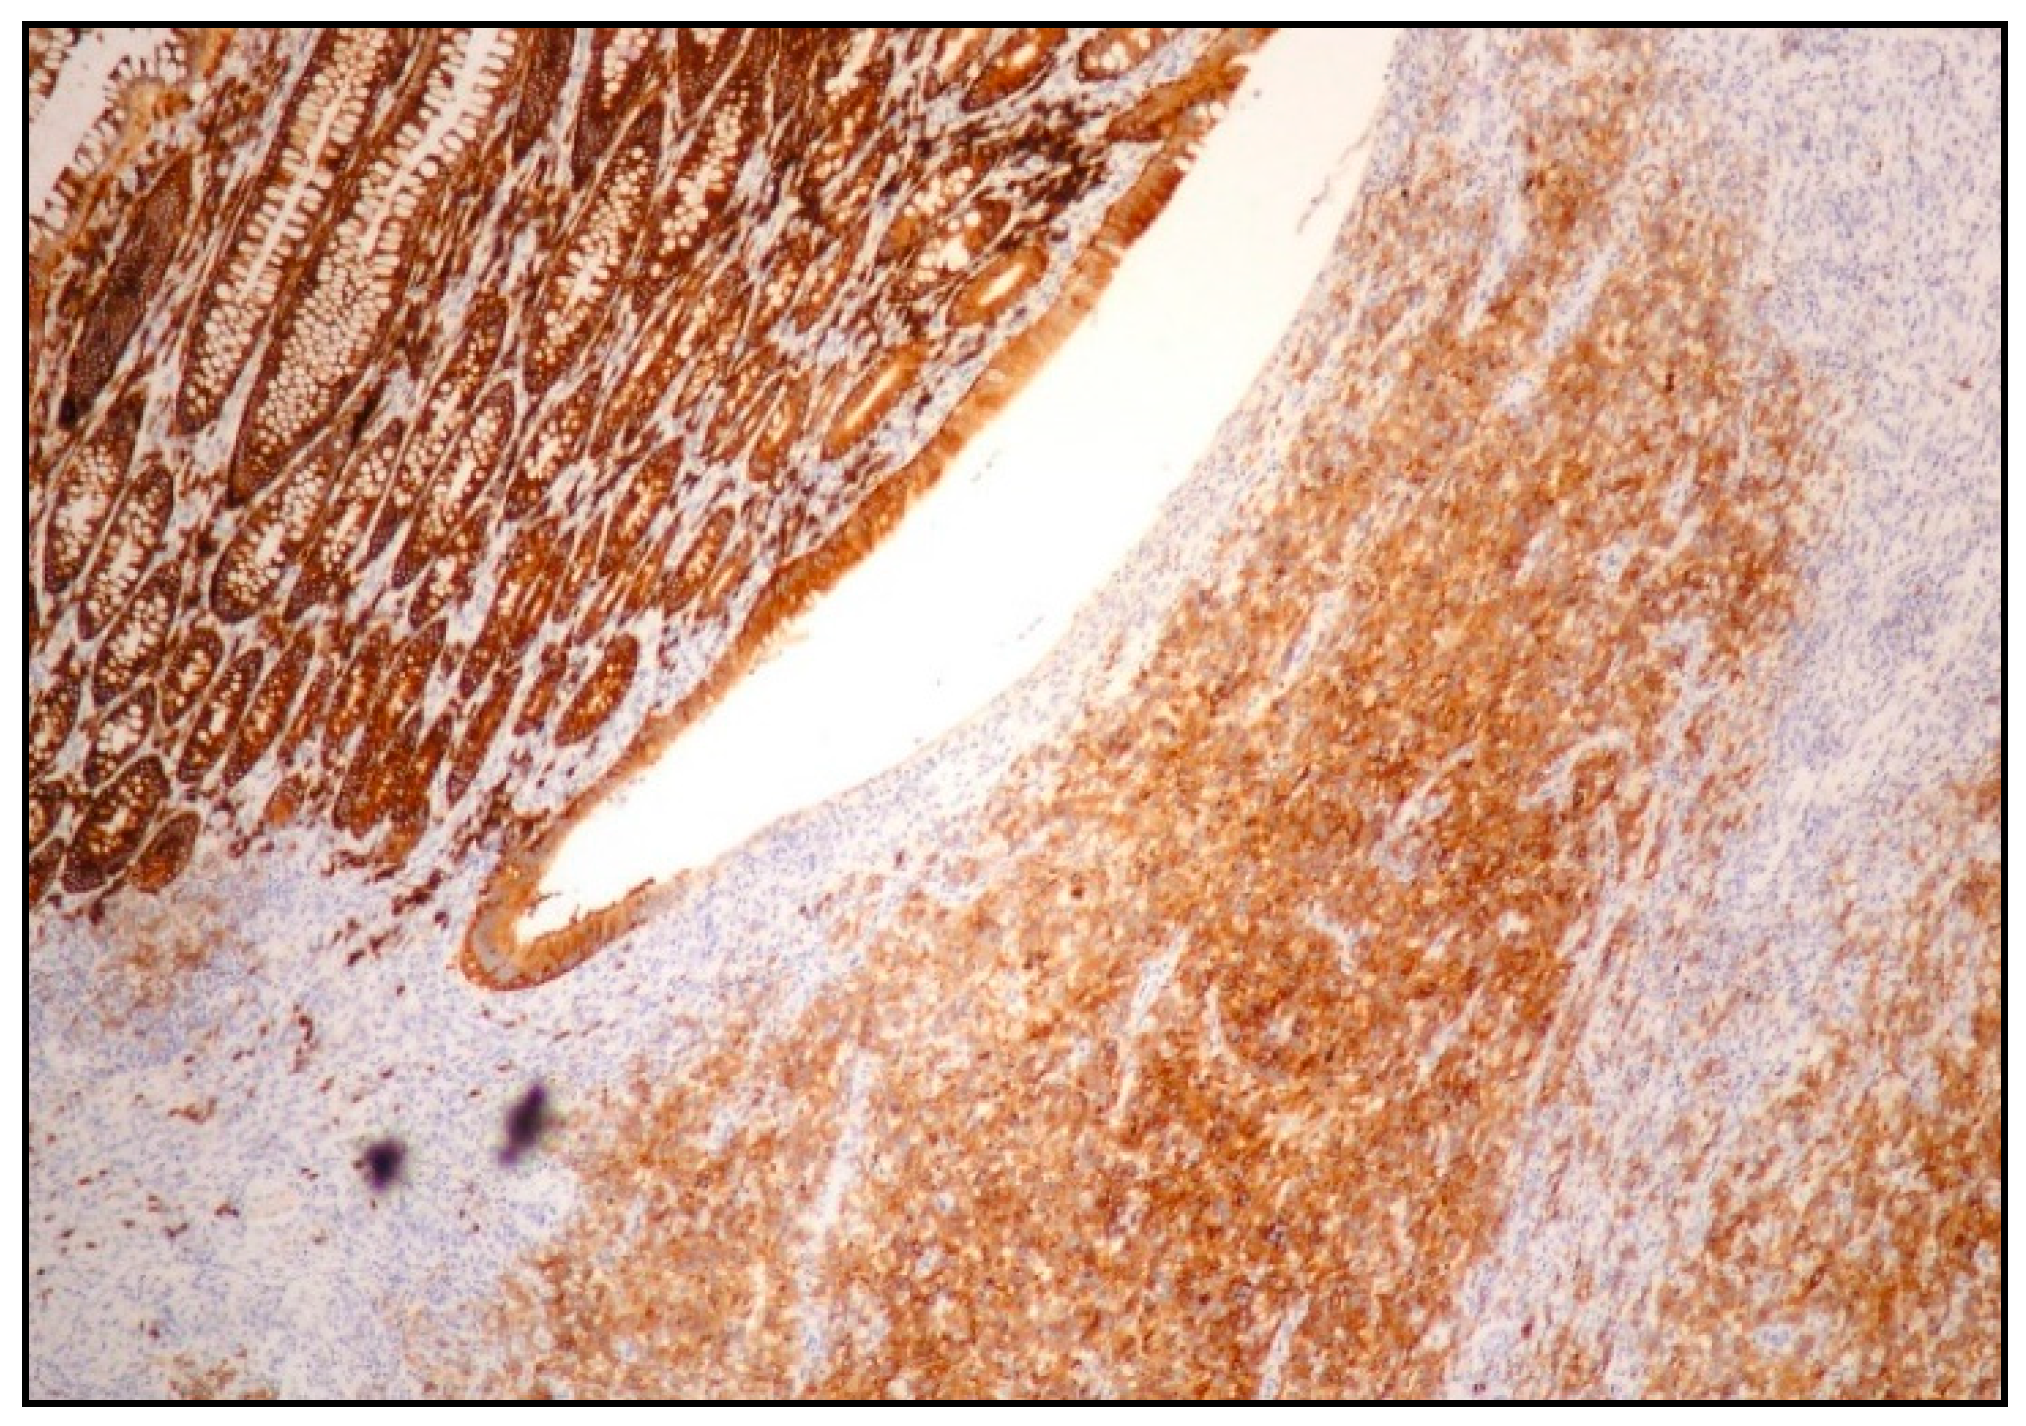

2.2. Morphology and Immunophenotype

4.2. Morphology, Immunophenotype and Molecular Features

| Histology | Large cells with IB and PB features | Diffuse proliferation of PBs/IBs | Sinusoidal and/or diffuse growth pattern of IBs and PBs | Sheets of PBs/IBs effacing organ architecture |

| CD20 | - (may be + in EC-PEL) | - or weakly + in a small number of cells | - (or weakly +) | +/− |

| PAX5 | - (may be + in EC-PEL) | - or weakly + in a small number of cells | - (or weakly +) | - |

| CD79alpha | - (may be + in EC-PEL) | + in 40% of cases | - (or weakly +) | - |

| MUM1/IRF4 | + | + | + | + |

| CD38 | + | + | + | −/+ |

| CD138 | + | + | + | - |

| CD30 | + | + | - | - (rarely +) |

| EMA | Often + | + | + | - |

| ALK | - | - | + | - |

| T-cell markers | Occasionally + (mainly in EC-PEL) | Occasionally + | + in half of cases (CD4) | - |